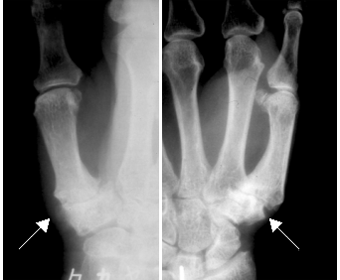

レントゲン検査でCM関節に「隙間が狭い」「軟骨が硬くなってトゲの様になっている(骨棘)」「亜脱臼」などの変形が見られた場合に、CM関節症と診断されます。